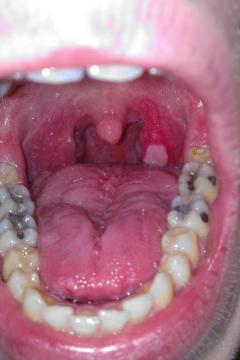

Biele fľaky v hrdle

Pro větší náhled klikněte na obrázek

Biele fľaky v hrdle Michal92 - 6.7.2014 14:09:53

Dobrý deň, prekonal som rozsiahlu infekciu hrdla, dosť ma bolela ľavá strana hrdla na ktorom sa mi vytvoril biely hnisavý fľak, a opuchli mi mandle na tejto strane Momentálne beriem antibiotik 10ty deň, mandľa odpuchla, aj bolesť hrdla sa stratila no ten fľak na hrdle stále mam. Antibiotika ešte na 5 dni mám, 2x denne kloktam šalviový čaj. Viete mi prosím poradiť čo by ešte prispelo k rýchlejšiemu vyliečeniu hrdla ? Ďakujem

Dobrý den, omlouvám se za zpožděnou odpověď, nejdůležitější je, že klinicky se cítíte lépe. Zopakovala bych stěr z krku, mezitím pokračovala v antibiotikách a kloktání.